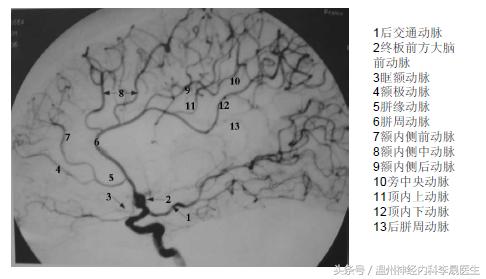

首先看看前动脉的供血区域,左图红色,右图绿色区域就是大脑前动脉的供血区域

细分前动脉的分支(关注我晚上发的大脑前动脉思维导图)

(一)中央支

1)反支(Heubner动脉)

2)基底支

(二)皮层支

1)眶后动脉通常在前交通动脉前方4-5mm处与大脑前动脉主干呈锐角发出,越过直回后部入嗅沟内,分布至眶部后内侧

2)眶前动脉分布至眶前内侧部

3)额极动脉分布于额极内、外侧面

4)额前内侧动脉

5)额中间内侧动脉

6)额后内侧动脉

7)旁中央动脉

8)楔前动脉

9)胼胝体动脉

(三)前交通动脉